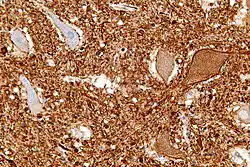

Micrograph of the anterior horn of the spinal cord showing motor neurons with central chromatolysis. Neurofilament immunostain.

Central chromatolysis is a histopathologic change seen in the cell body of a neuron, where the chromatin and cell nucleus are pushed to the cell periphery, in response to axonal injury.[1][2] This response is associated with increased protein synthesis to accommodate for axonal sprouting. In addition to traumatic injuries, central chromatolysis may be caused by vitamin deficiency (pellagra[3]).